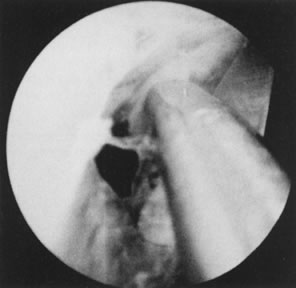

Although large endometrial polyps, particularly when pedunculated, are easily removed by hysteroscopic guidance, the removal of submucous leiomyomas requires more experience. Several methods are available. When the leiomyoma is smaller than 2 to 3 cm and is pedunculated, mechanical transection of the pedicle expedites its removal. Nonetheless, myomas larger than 3 cm with thick pedicles, or sessile myomas, must be removed by segmental shavings with a resectoscope and a cutting loop. This is performed systematically until the uterine wall is reached, when resection should stop. With experience, the endoscopist learns tactile appraisal provided by the resecting loop to distinguish fibrous myomatous tissue from myometrium. In addition, he or she can visually appraise the fibrotic tissue and the fascicularis aspect of the myometrium. When myomas penetrate deeply into the uterine wall, laparoscopy should be considered to monitor the hysteroscopic-resectoscopic operation transabdominally (Color Plate 1A to F; Figs. 21, 22, 23, 24, 25, and 26).8–17

Fig. 21. Hysterosalpingogram shows an occupying lesion distorting the uterine cavity symmetry.

Fig. 22. Hysteroscopic view of pedunculated submucous myoma.

Fig. 23. Hysteroscopic dissection/removal of myoma with scissors.

Fig. 24. Myoma specimen after resection.

Fig. 25. Follow-up hysterosalpingogram shows normal uterine cavity.

Fig. 26. Large, sessile submucous myoma being resected with wire-loop electrode.